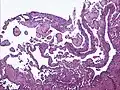

Low power photomicrograph of an endovascular papillary angioendothelioma showing papillae with hyalinized cores

High power view showing a vascular tumor with cuboidal endothelium lining the vessels. Few entrapped seminiferous tubules are also noted (arrow).

Characteristic budding, hobnail-like endothelial cells visible.